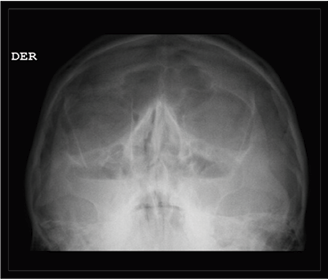

Se solicita radiografía de senos paranasales en la cual se observan niveles hidroaéreos en ambos maxilares sugestivos de senositis maxilar (Figura 1). Así mismo, se solicita tomografía pulmonar en la que se evidencia dextrocardia con imágenes de vidrio despulido y árbol en gemación. Por lo tanto, se realiza broncoscopia en que se observan cuerdas vocales con adecuada movilidad, sin presencia de secreciones. Se realiza toma de biopsia transbronquial y muestras de lavado bronquialveolar para su posterior análisis microbiológico, el cual reporta cultivo negativo. También se realiza gen expert para tuberculosis con resultado negativo. Con estos hallazgos clínicos y radiológicos se diagnostica a la paciente con un síndrome de Kartagener completo.

Figura 1.

(A) Radiografía de senos paranasales en proyección waters en la cual se observan senos maxilares con nivel hidroaéreo y velamiento perimetral. (B) Tomografía torácica ventana pulmonar, corte axial en la que se observa dextrocardia e imágenes en vidrio deslustrado y áreas de árbol en gemación ubicadas en la língula, (C) y (D) cortes coronales con imágenes de bronquiectasias cilíndricas para hiliares bilaterales (página siguiente).